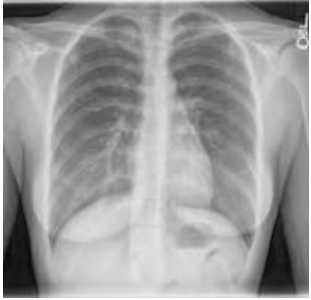

A 58-year-old woman was refered to our hospital with a history of recurrent right side chest wall pain ,cough ,night sweating ,hemoptysis and dyspnea for 4-6 weeks. A physical examination revealed respiratory sounds were decreased on the middle right side of chest. His complete blood count, erythrocyte sedimentation rate, CRP blood urea nitrogen (BUN) level, and creatinine level were normal and liver function tests (AST,ALT ,AKP and bilirubin ) and anti hydatid tests were normal . Poster anterior (PA) and lateral chest radiographs were performed . The PA chest radiograph (Figure 1)showed a well-defined 10- to 14-cm right paracardiac cystic mass located in the right middle zone of chest. The CT-scan showed a large well –defined hypo dense cystic mass measuring 112 mm is seen in superior segment of RUL.Sub segmental atelectasis also seen in right lung caused compressing. Left lung was normal . Figure 2(a,b,c,d,e,f,g,h,i) . In the CT –scan there was no invasion of the chest wall and others intrathoracic structures. CT images show no enlargement of lymph nodes and pleural effusion but lung parachymal was involved.The testes for hydatid cyst were negative .Ultrasonography of abdomen was normal . A classic right posterolateral thoracotomy in six intercostal space was performed. Around of cystic lesion was walling off with wet sponge with normal Saline (Fig 3). In the aspiration of the lesion there was a hemorrhagic dense viscous fluid .The cystic mass was completely removed without complications and free margin. On the operation time , macroscopic examination show hemorrhagic dense viscous fluid and debris was observed in the center of the lesion(Fig 4) Microscopic examination showed an encapsulated mesenchymal neoplasm composed of short fasciles of bland looking spindle cell which are diffusely positive for S100 and GEAP on immunohistochemically diagnosis was a schwannoma tumor. The patient was discharged on the 6 th postoperative day. The patient did not recurrence after 8 month of follow-up

Figure: 1 CXR show right side lung cyst.